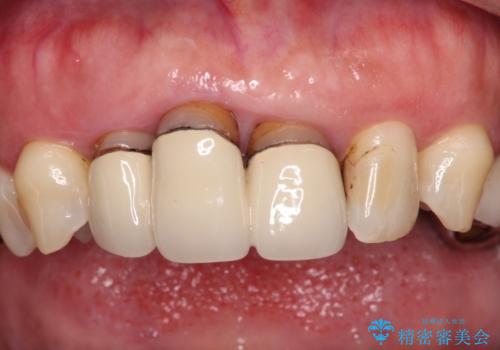

- 20年以上前に装着した前歯のメタルセラミックが不自然であることを気にして来院された患者様です。

歯肉の位置が変わり、変色した歯根が露出しているため、金属の土台をファイバーコアに交換した上で、オールセラミッククラウンにて補綴することとしました。